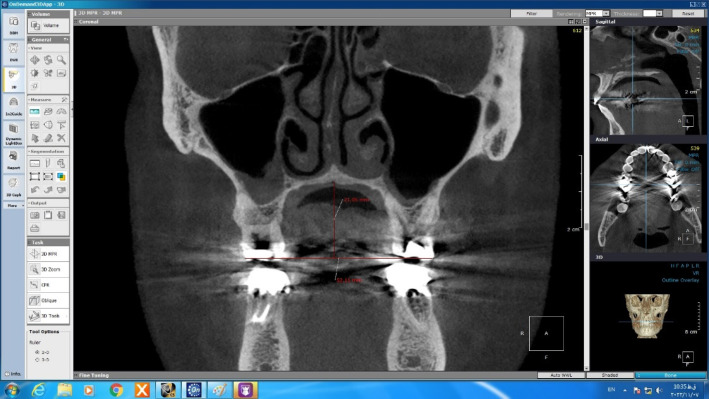

Methods: CBCT records taken during 2020-2022 of 120 patients were obtained to investigate the relationship between impacted canine and maxillary morphology as well as sinus dimensions. The CBCT images were then divided into three groups: control, unilaterally canine impaction and bilaterally canine impaction. Then morphology-related variables (arch circumference, arch length, inter molar width, inter first premolar width, palatal depth, anterior posterior dimension of the right and left sinuses, and mediolateral dimension of the right and left sinuses) were analyzed and compared between groups. All measurements were done by Ondeman 3D dental software. Statistical analysis was carried out by SPSS software version 21 using one-way ANOVA.

Results: There were meaningful differences in patients with canine impaction compared with control group in arch circumference (P value= 0.004) and arch length (P value= 0.001), inter molar width (P value= 0.001), inter first premolar width (P value= 0.001), mediolateral dimension of the right (P value=0.001) and left (P value= 0.001) sinuses of maxilla. Furthermore, Palatal depth and anterior posterior dimension of the right and left sinuses did not show statistically significant difference between groups.